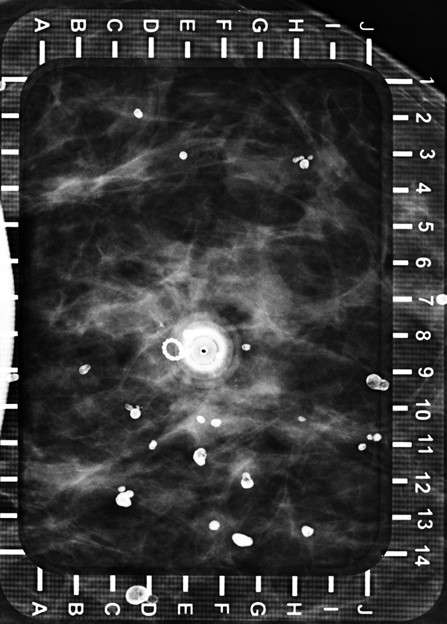

Technologist obtains orthogonal image of the breast (Figure 3).

Radiologist adjusts needle depth and then deploys wire, with tip between 0.5 – 1.0 cm deep to the lesion or as indicated based on surgeon preference. An image is taken to confirm wire tip location, then the needle(s) may be removed.

Procedure Mammographically Guided Wire Localizations Figure 3

Figure 3: Spot mediolateral (ML) view of the needle in the same patient.